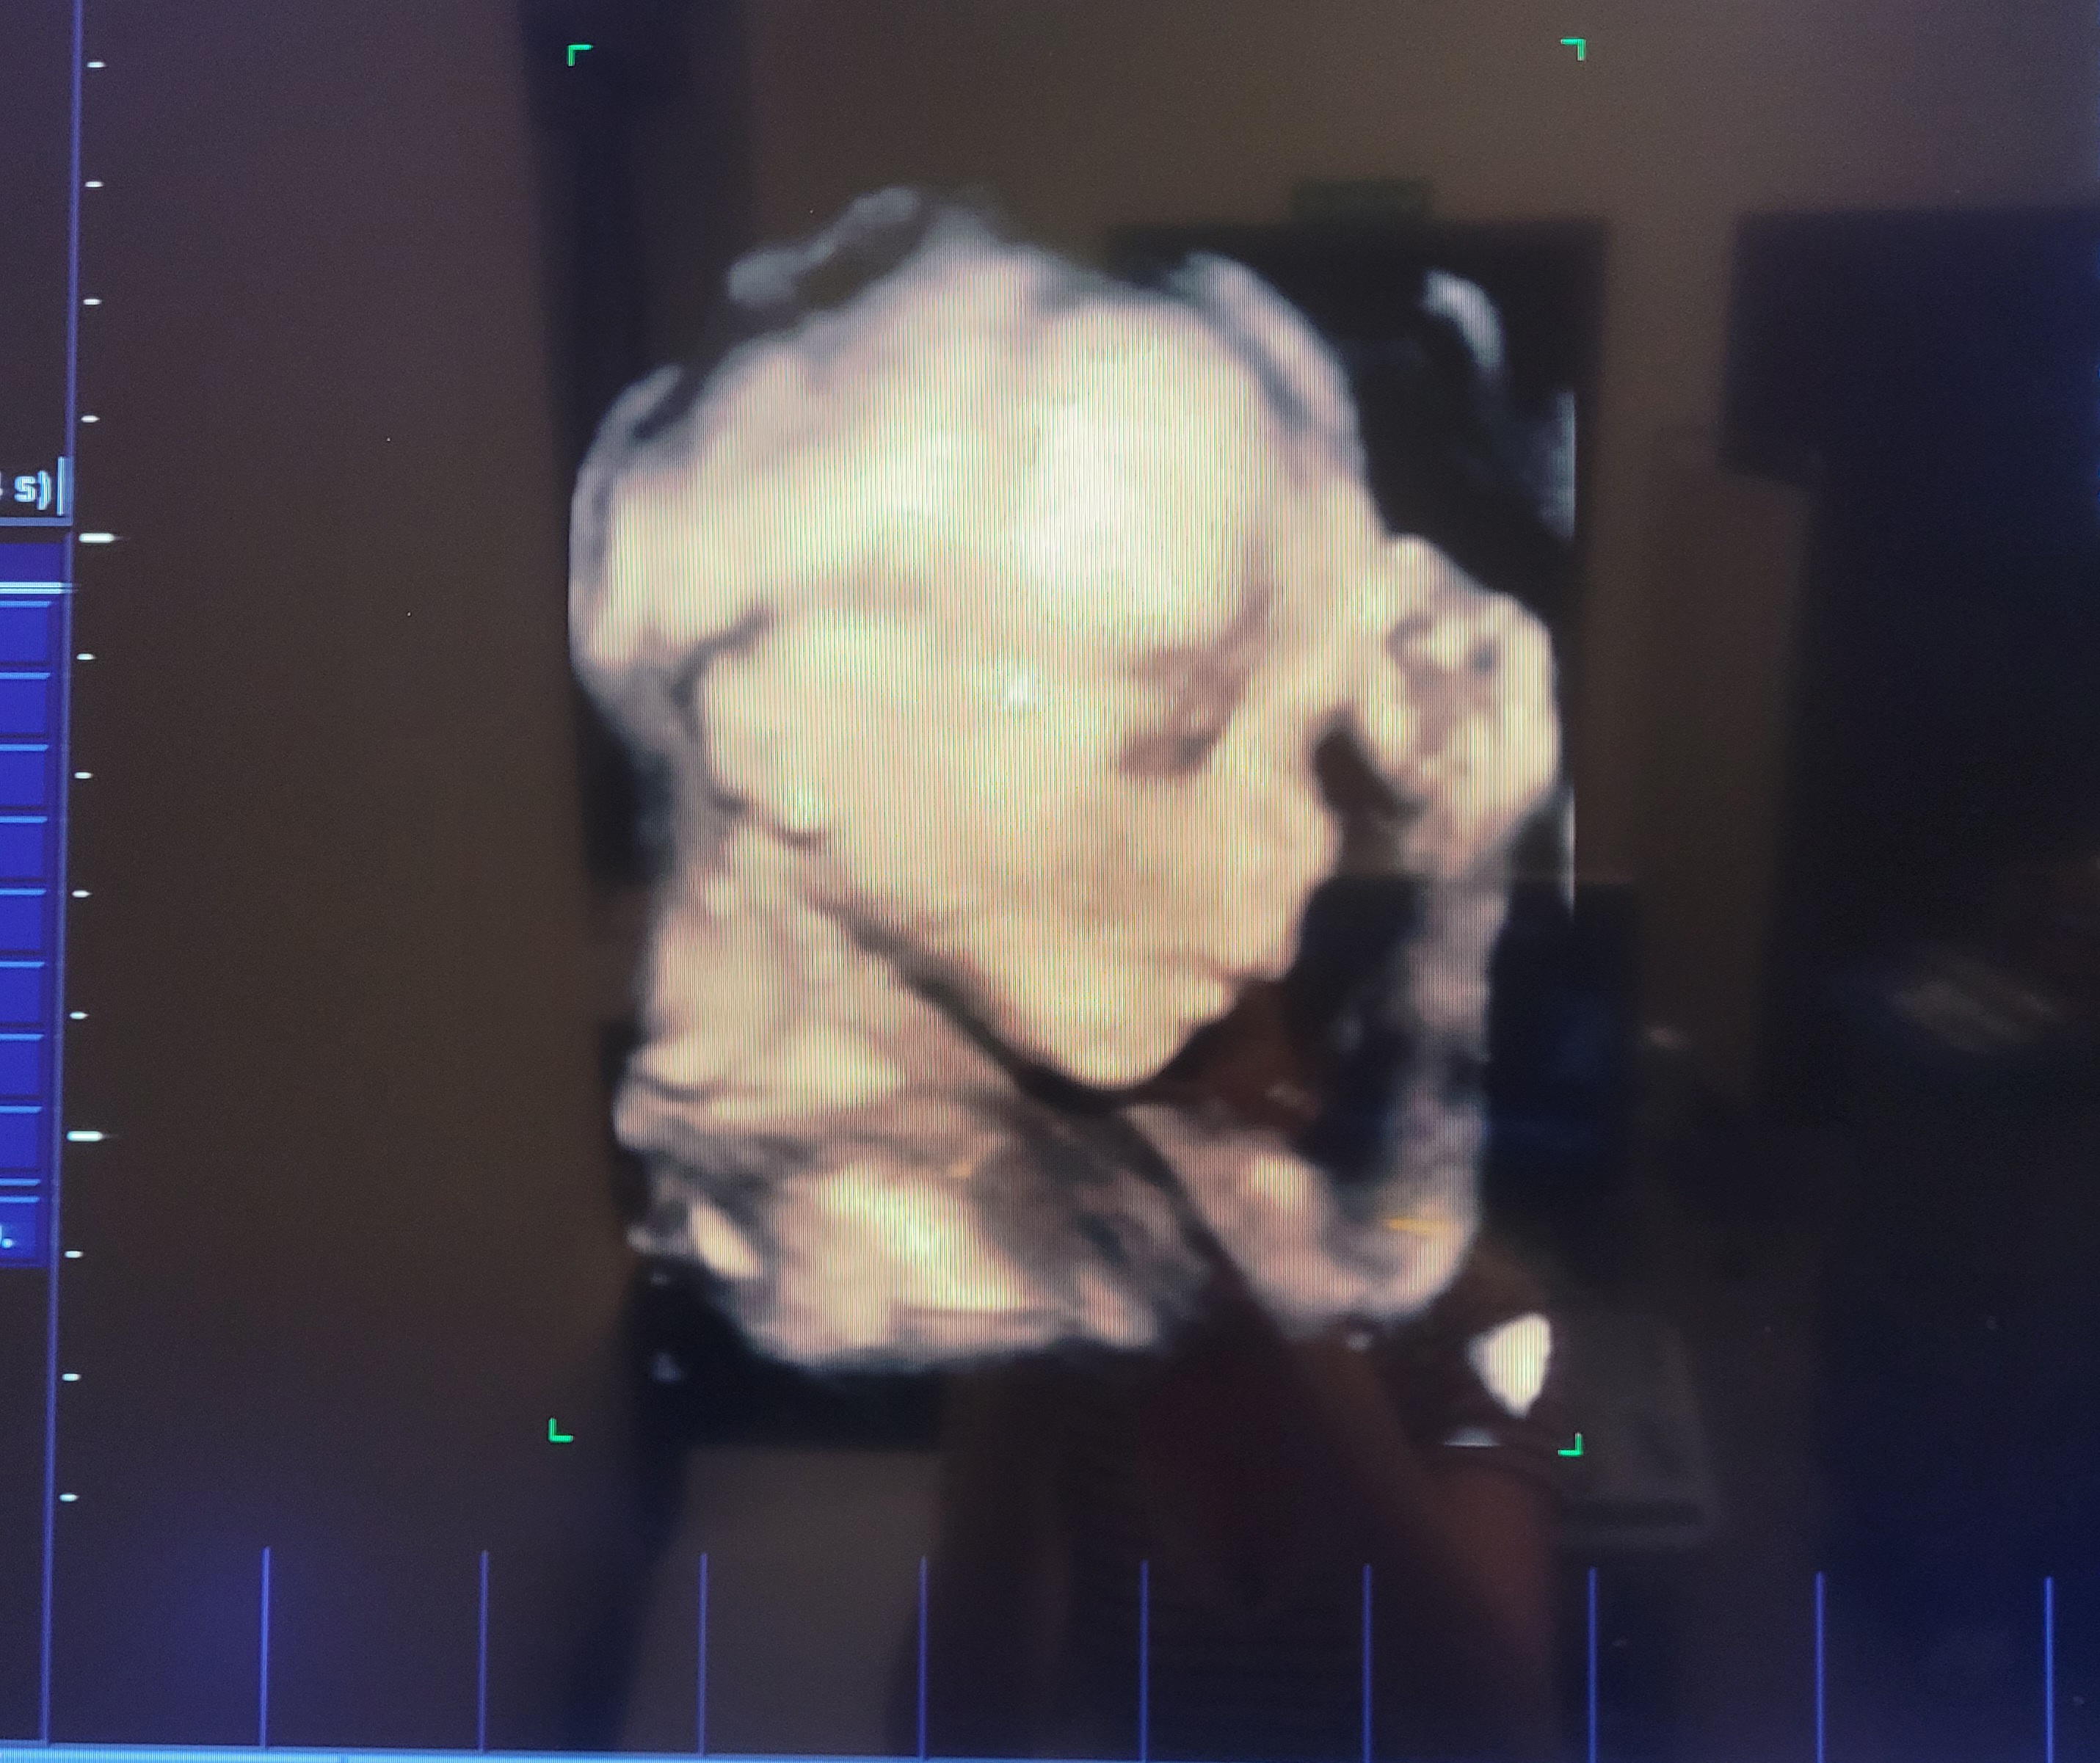

Ja już po wizycie. Z synkiem wszystko super. Niestety szyjka zaczęła mi się skracać, miałam 4 cm a teraz 3,2 cm. Mam nakaz odpoczywania, drzemek i oszczędzania się. Mam nadzieję, że to pomoże bo trochę zaczęłam się stresować 🫣

Wrzucam fotkę młodego z dzisiaj ✨️

@Flora lez i odpoczywaj. Ale masz piekne zdjecie! Szyjka była mierzona zawsze tym samym usg i przez tego samego lekarza? Bo czasami zmiana sprzetu moze dawac takie rozbieznosci. Ja tak raz na patologii wyladowalam a okazalo sie ze pomiar był źle zrobiony.👩🏻🦰41🧔🏻39